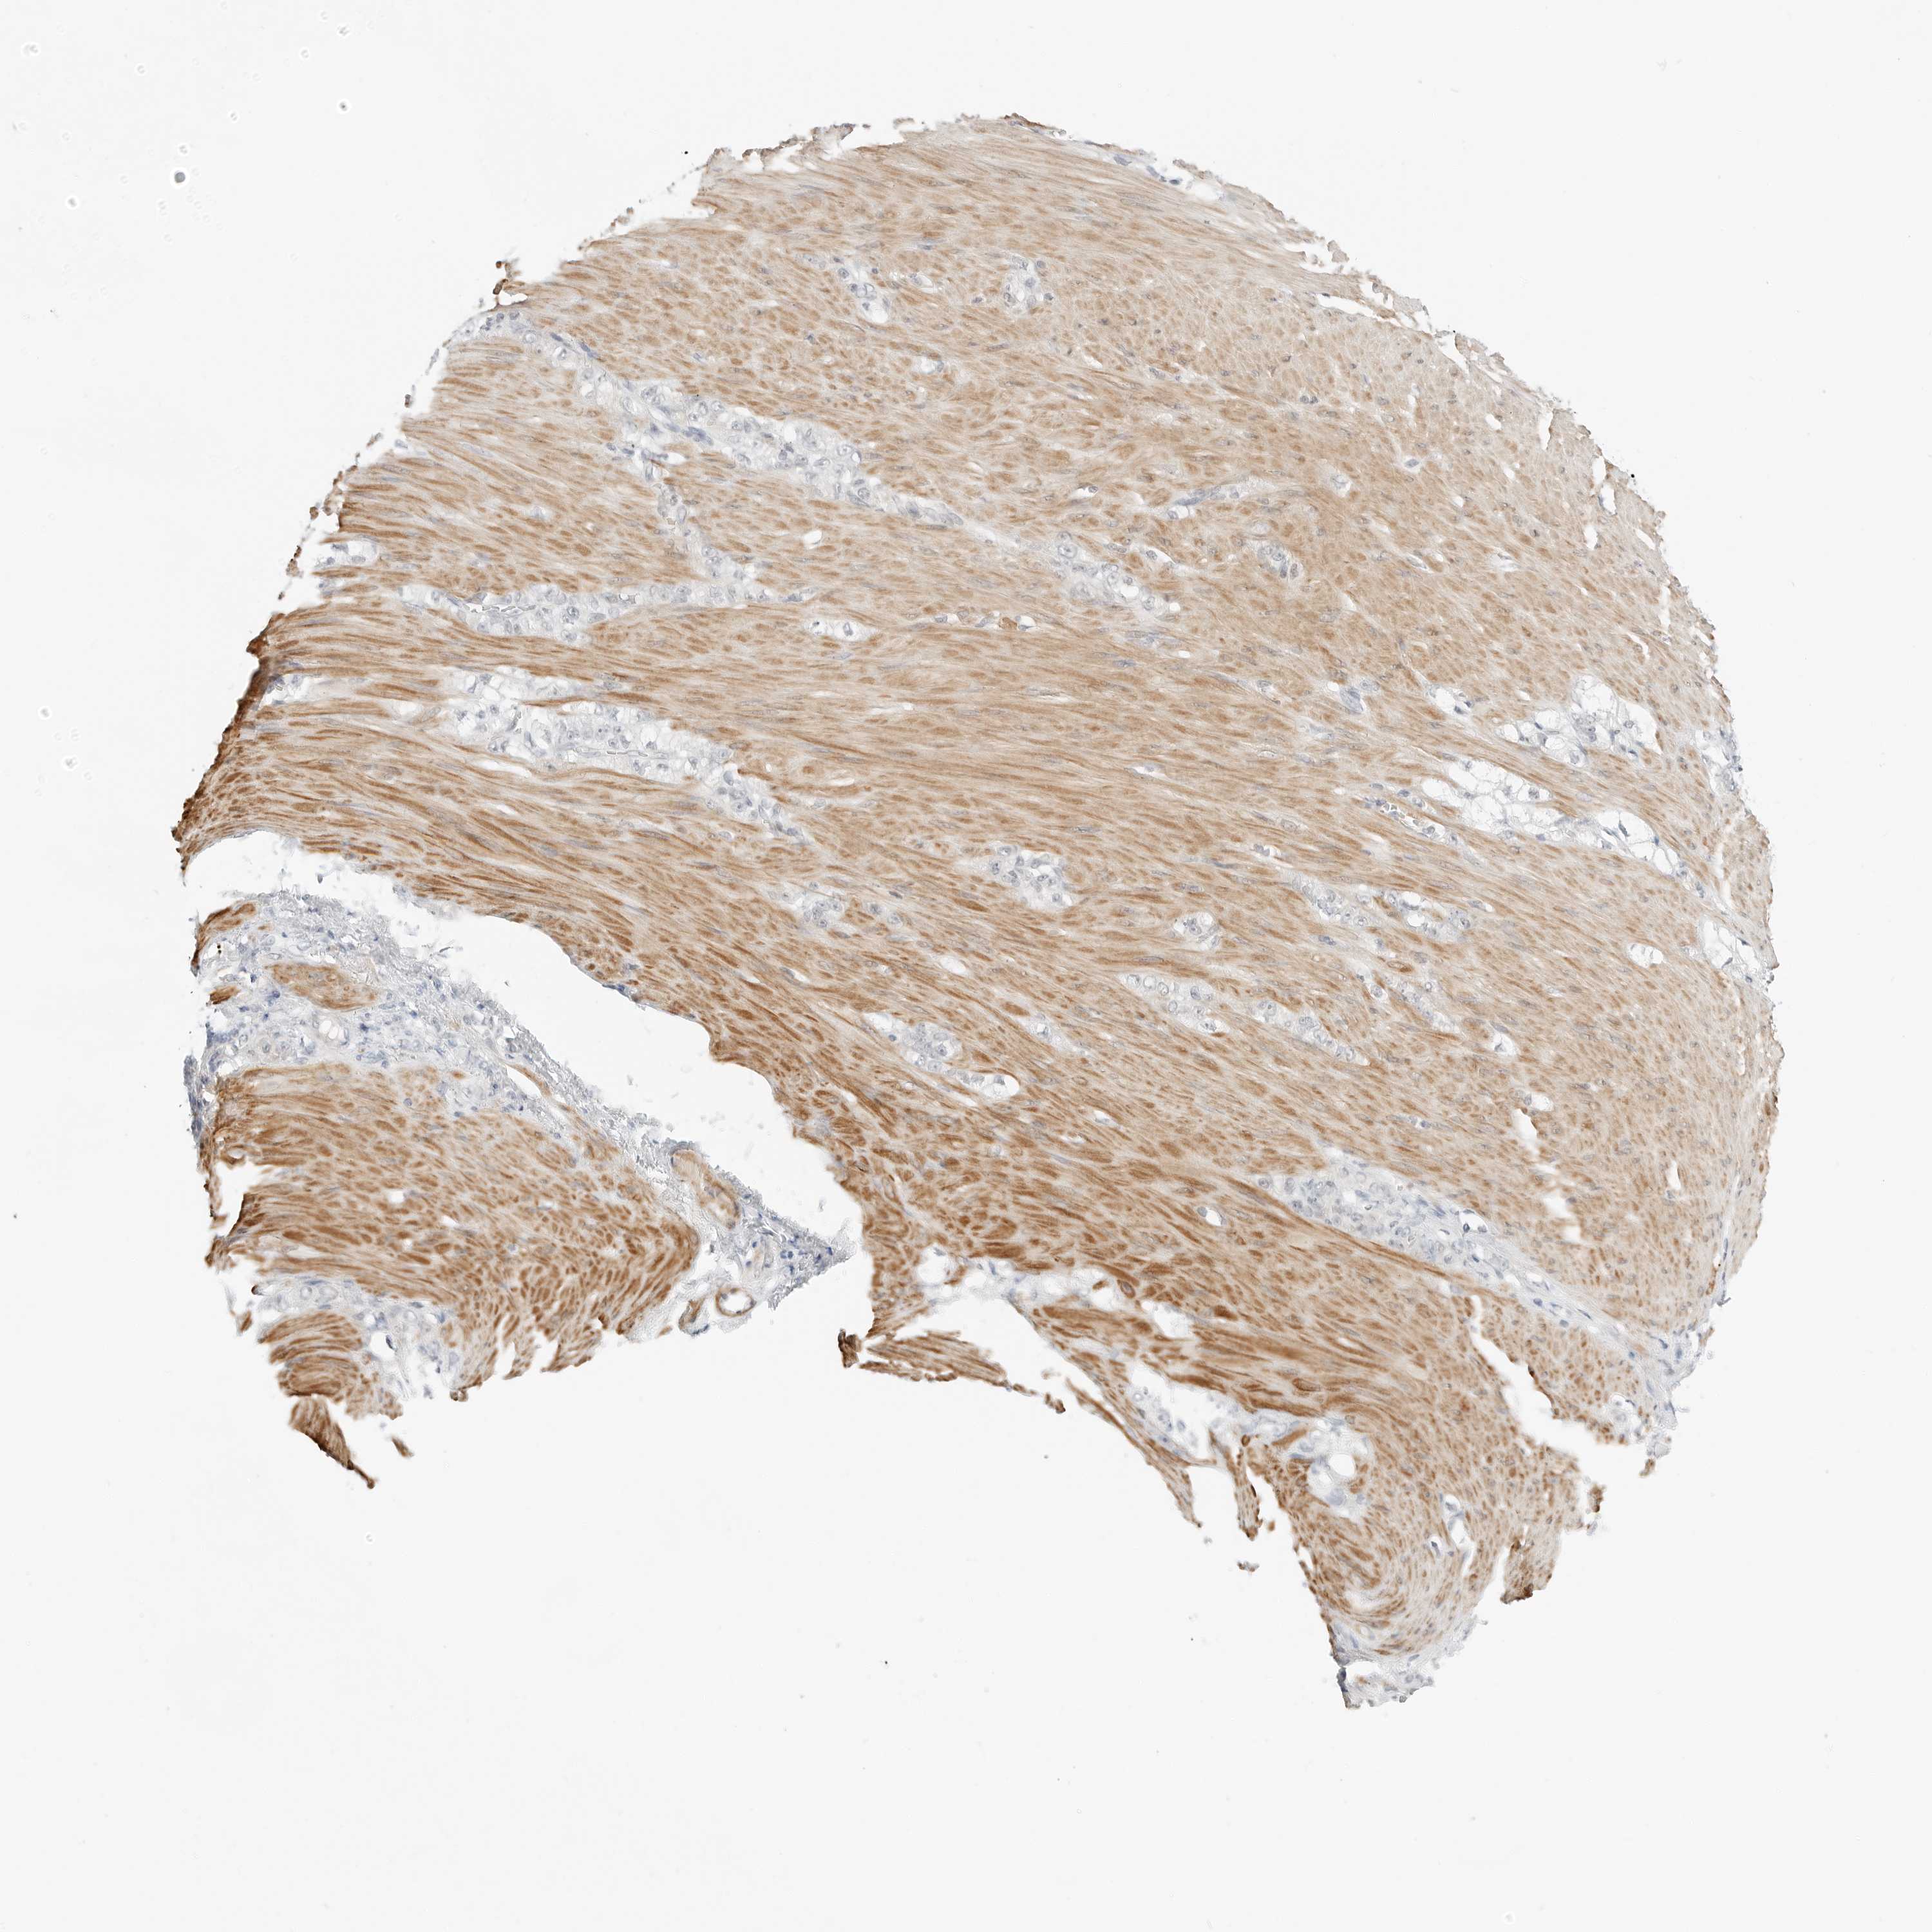

STOMACH CANCER - Protein expressioni

A mouse-over function shows sample information and annotation data. Click on an image to view it in a full screen mode. Samples can be filtered based on level of antibody staining by selecting one or several of the following categories: high, medium, low and not detected. The assay and annotation is described here.

Note that samples used for immunohistochemistry by the Human Protein Atlas do not correspond to samples in the TCGA dataset.

Antibody stainingi

Antibody staining in the annotated cell types in the current human tissue is reported as not detected, low, medium, or high, based on conventional immunohistochemistry profiling in selected tissues. This score is based on the combination of the staining intensity and fraction of stained cells.

Each image is clickable and will lead to virtual microscopy that enables deeper exploration of all samples and also displays staining intensity scores, fraction scores and subcellular localization as well as patient and tissue information for each sample.

Antibody HPA028602

Antibody HPA028686

Staining

High

Medium

Low

Not detected

Intensity

Strong

Moderate

Weak

Negative

Quantity

>75%

75%-25%

<25%

None

Location

Nuclear

Cytoplasmic/membranous

Cytoplasmic/membranous,nuclear

Adenocarcinoma, NOS